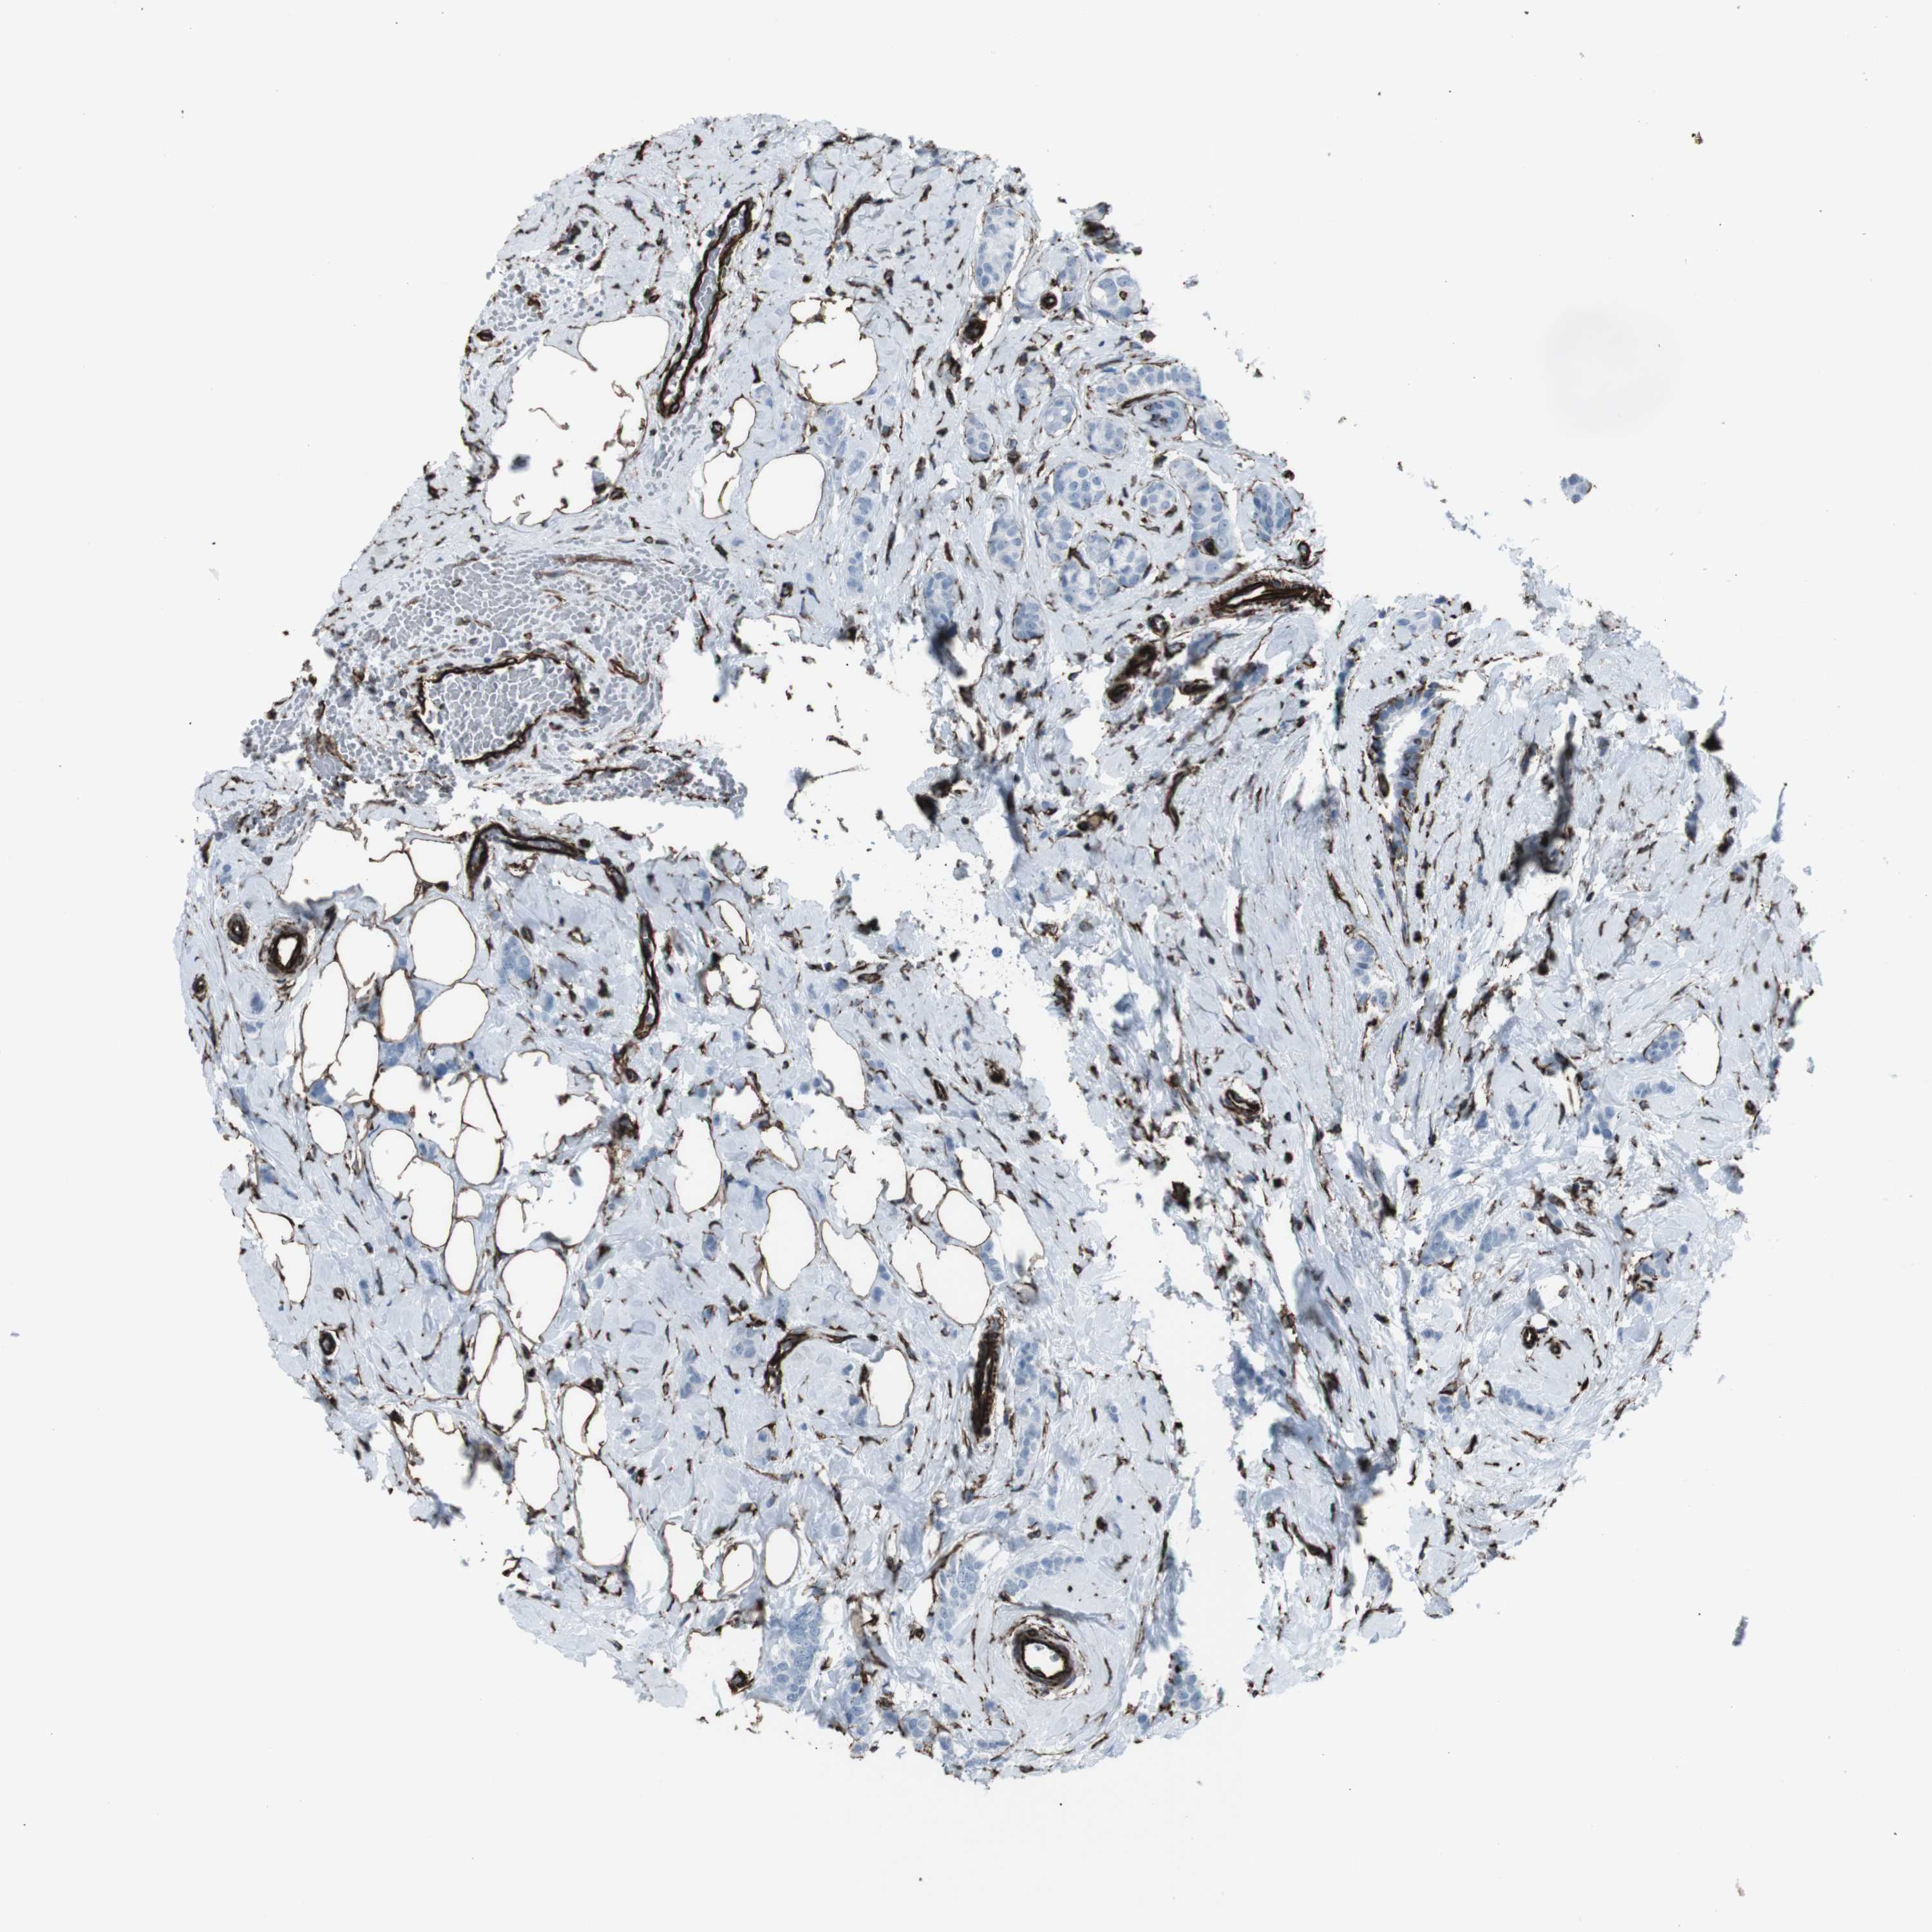

CANCER BREAST CANCER Show tissue menu

BRCA TCGA BRCA VALIDATION PROTEIN EXPRESSION